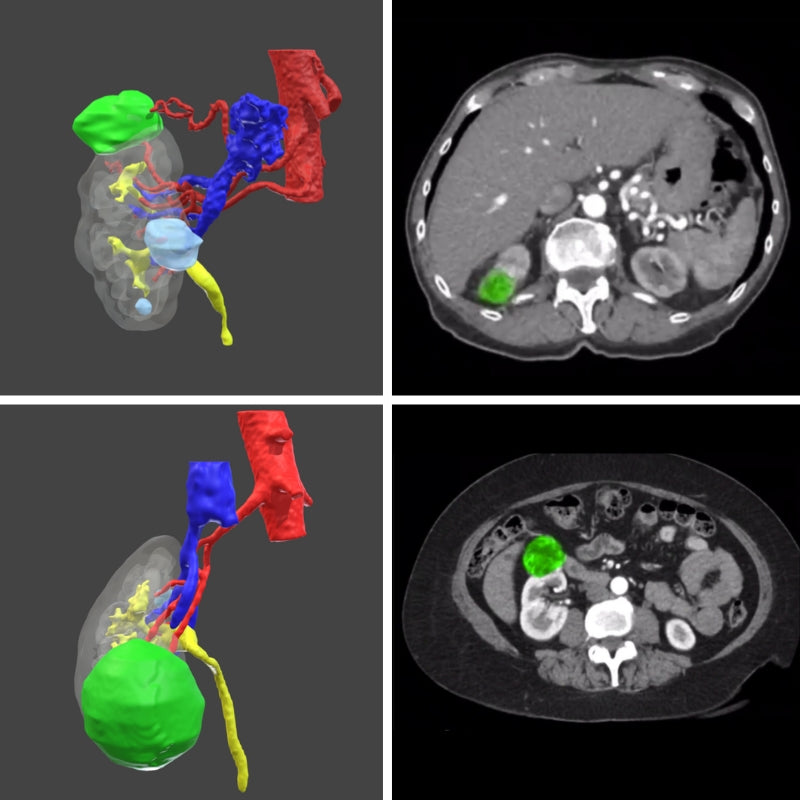

Surgical planning - Digital 3D model for urology

Surgical planning - digital model

Only for urology

Plan your next surgery with a 3D model of the patient's exact anatomy. This planning is done based on the CT scans.

Once the images are sent, the process takes between 10 to 17 business days.